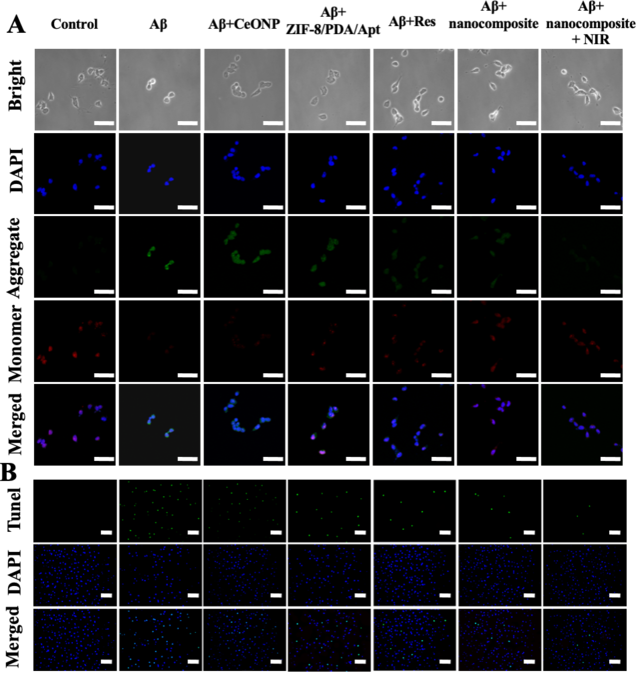

ТѕЉС╗гжњѕт»╣A╬▓УЄфуЙцжЏєуџётЙЂУ▒А��№╝їУђЃт»ЪС║єУ»ЦТјбжњѕтюеТіЉтѕХA╬▓уЙцжЏєС╗ЦтЈіУДБуд╗тјЪу║цу╗┤Тќ╣жЮбуџёуќЌТЋѕ�сђѓThTтњїTEMТЋѕТъюТЅ╣Т│е№╝ѕтЏЙтЏЏ№╝Ѕ��№╝їТјбжњѕТЌбУЃйтцЪТіЉтѕХA╬▓тЇЋСйЊуЙцжЏє��№╝їтЈѕУЃйУДБУЂџA╬▓тјЪу║цу╗┤��№╝їт╣ХСИћтюетЁЅуЃГуЁДт░ёСИІ��№╝їУ»ЦТђДУЃйУЃйтцЪУјитЙЌтбът╝║�сђѓу╗єУЃътєЁТ▓╗уќЌТЋѕТъюТЅ╣Т│е��№╝їУ»ЦТјбжњѕУЃйтцЪтюеу╗єУЃъТ░┤т╣│��№╝їТюЅућеТіЉтѕХA╬▓тЇЋСйЊуЙцжЏє��№╝їТЅФжЎцA╬▓OУ»▒т»╝уџёу╗єУЃътєЁУ┐ЄжЄЈROS��№╝їт╣ХСИћТјбжњѕуџётЁЅуЃГТђДУЃй��№╝їУЃйтцЪтбът╝║тЁХТ▓╗уќЌТЋѕТъю№╝ѕтЏЙС║ћ№╝Ѕ�сђѓтѕФуџё��№╝їJC-1сђЂTUNELС╗ЦтЈіCalcium-AM/PIТЪЊУЅ▓ТЋѕТъютЮЄТЅ╣Т│е��№╝їУ»ЦТјбжњѕтЈ»С╗ЦТюЅућетю░��№╝ЏсЂЕуфгУх┤т║ЦУ┤Ј╬▓У»▒т»╝уѕєтЈЉуџётЄІС║А�сђѓ

ТюгТќЄТЅђТъёт╗║уџёРђюТаИ-тБ│РђЮCeONP-Res-PCM@ZIF-8/PDA/Aptу║│у▒│У┤еТќЎ��№╝їУЃйтцЪжђџУ┐ЄУЇДтЁЅтЁ▒Тї»УЃйжЄЈУйгуД╗��№╝їт«ъуј░т»╣A╬▓OуџёУЇДтЁЅТБђТхІ��№╝їСИћуЅ╣т╝ѓТђДт╝║сђЂУ┐ЁжђЪт║джФў��№╝їУЃйтцЪтюеу╗єУЃъТ░┤т╣│ТБђТхІA╬▓Oт╣ХуЏЉТхІA╬▓OуЌЁуљєтИїТюЏ�сђѓтЈдСИђТќ╣жЮб��№╝їУ»ЦТјбжњѕтЁиТюЅС╝ўт╝ѓуџётЁЅуЃГУйгТЇбТђДУЃй��№╝їт╣ХтЁиТюЅжФўУййУЇ»ујЄ��№╝їУЃйтцЪт«ъуј░NIRтЈ»ТјДуџёResжЄіТћЙ�сђѓСйЊтцќСИју╗єУЃъТ░┤т╣│т«ъжфїТЅ╣Т│е��№╝їУ»ЦТјбжњѕтюеROSТЅФжЎцсђЂТіЉтѕХA╬▓тЇЋСйЊуЙцжЏєсђЂУДБУЂџA╬▓у║цу╗┤Тќ╣жЮбТўЙуц║тЄ║С║єС╝ўт╝ѓуџёТ▓╗уќЌТЋѕТъю��№╝їт╣ХСИћУЃйтцЪТюЅућетю░��№╝ЏсЂЕуфгУх┤т║ЦУ┤Ј╬▓У»▒т»╝уѕєтЈЉуџётЄІС║А��№╝їт╣ХтюеNIRтѕ║Т┐ђСИІ��№╝їУ┤еТќЎуџётЁЅуЃГТђДУЃйУЃйтцЪУ┐ЏСИђТГЦтбът╝║Т▓╗уќЌТЋѕТъю�сђѓ